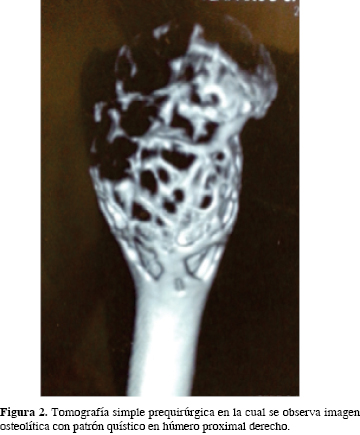

Radiológicamente, el QOA es una lesión multiquística, expansiva y excéntrica con reacción perióstica, con un patrón geográfico de destrucción ósea y trabeculación al interior.1 Para completar el diagnóstico se utiliza la TAC (tomografía axial computarizada) que muestra niveles líquidos y gammagrafía ósea que refleja la naturaleza vascular de la lesión.1

Se trata de una paciente del género femenino de 7 años de edad, sin antecedentes de importancia para el padecimiento actual, quien sufre una caída desde su plano de sustentación e ingresa por contusión directa en hombro derecho, dolor, aumento de volumen en húmero proximal y limitación funcional. Fue manejada con analgésicos no esteroideos sin mejoría. La radiografía simple mostró lesiones líticas y trabeculares en húmero proximal derecho (Figura 1), la tomografía axial simple, una imagen osteolítica con patrón quístico difuso en metáfisis proximal de húmero por debajo de la fisis (Figura 2) y el gammagrama óseo con aumento de la captación compatible con proceso tumoral en húmero proximal sin metástasis. La fosfatasa alcalina fue de 290 UI/l (normal 44 a 147 UI/l), deshidrogenasa láctica de 65 UI/l (normal 60 a 70 UI/l), calcio sérico de 10 ng/dl (normal 8.9 a 10.1 mg/dl); resto de estudios dentro de parámetros normales. El resultado histopatológico reportó quiste óseo aneurismático. Fue manejado con legrado y resección intralesional con técnica eggshell, colocación de injerto óseo autólogo de peroné izquierdo libre no vascularizado y estabilización con clavo centromedular de Steinman el cual se retiró a las 12 semanas posteriores. A los cuatro años la paciente, está asintomática, sin evidencia de recidiva de la lesión por tomografía axial computarizada (Figura 3) y con regeneración total del sitio de toma del injerto peroneo (Figura 4).